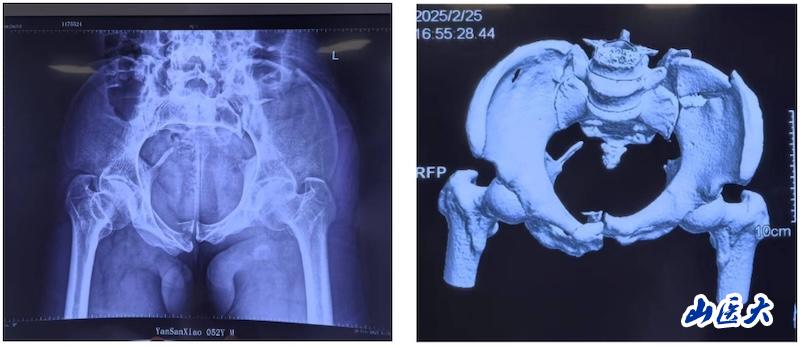

术前

该患者在驾驶三轮车时发生车祸,导致骨盆骨折,经过当地医院对症治疗后转入我校第二医院急诊科。由于血色素持续下降,血管外科首先进行了血管介入栓塞处理,随后转入骨科创伤病区,由孙海钰团队接续治疗。经过详细检查和评估,孙海钰主任、贺冬冬副主任医师、王欢副主任医师为患者制定了运用UCRT解锁复位技术,结合天玑机器人及O-arm术中影像系统为其实施骨盆闭合复位的手术治疗方案。3月6日,孙海钰团队在骨科老一辈专家尹芸生主任的指导及麻醉师、技师、器械护士和巡回护士的通力协助下,成功运用微创新技术为患者实施了手术。